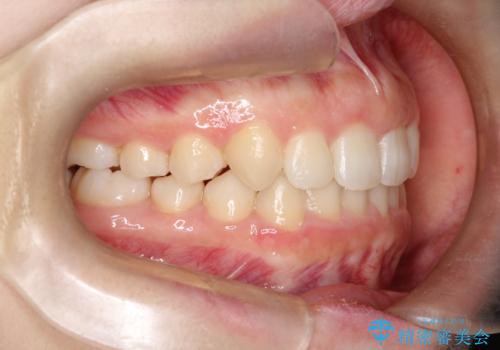

押しつぶされた歯列、アーチの拡大だけで非抜歯で改善した症例

初診時の歯並びの状態としては、上下ともに全体に及ぶの中等度以上のがたつき(叢生)があり、全額的に歯列のアーチが内側に押しつぶされた状態でした。

強い叢生がありましたが、抜歯は行わず上下顎ともに、主に歯列弓の拡大を行い叢生を改善しました。